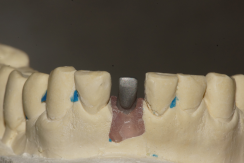

O análogo foi inserido no transferente, o molde foi vazado com gesso pedra especial e no laboratório foi realizada a confecção do coping metálico (Figuras 19 e 20).